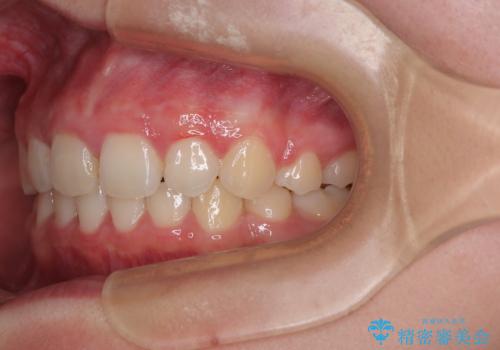

- 下唇の上に乗っかってしまうくらい前歯が飛び出していることを気にして来院された患者様です。

唇を閉じようとするとオトガイ部に力が入ってしまい、うまく閉じることができない状態であったため、上下左右の第一小臼歯4本を抜歯して、ワイヤー装置にて矯正治療を行うこととしました。

飛び出した前歯はしっかりと引っ込み、横顔の印象が大きく変化しました。